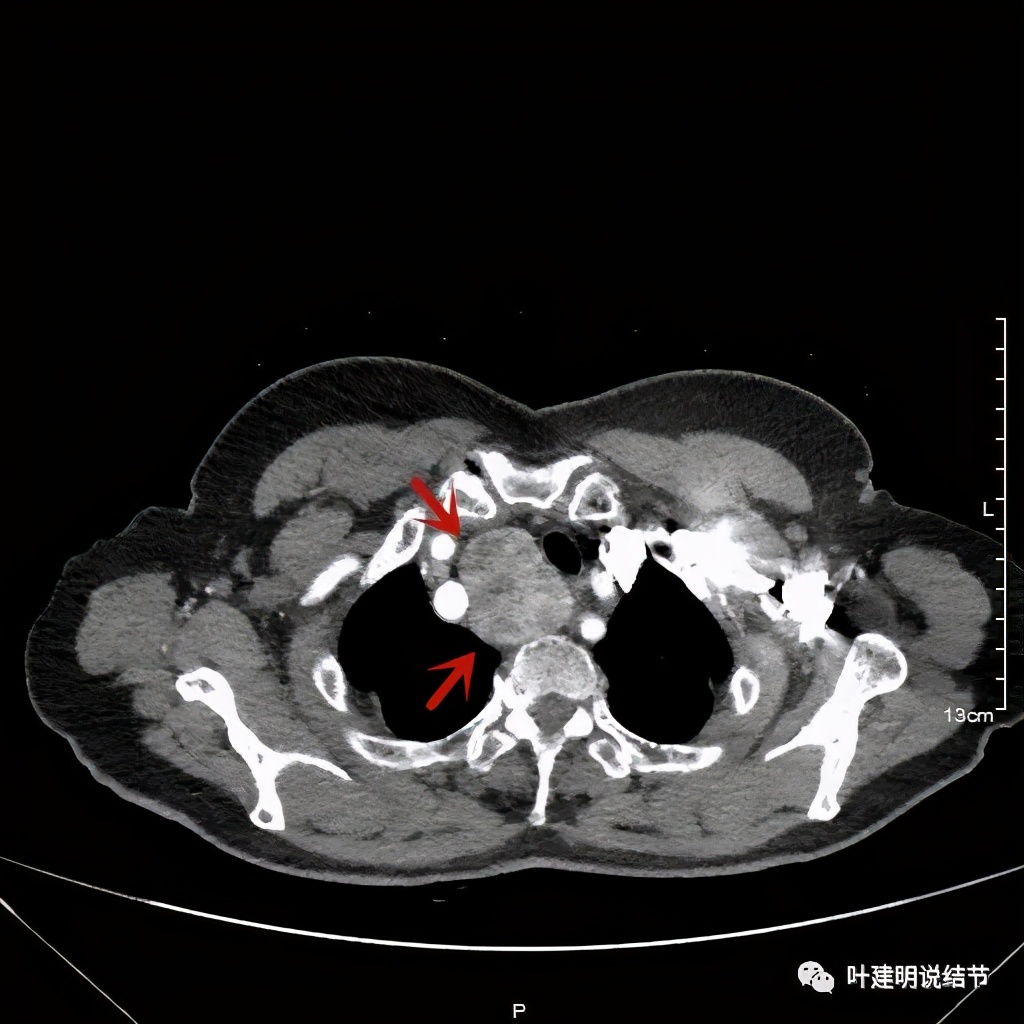

上图红色示肿瘤,黄色示气管,蓝色示上腔静脉

上图红色示肿瘤,黄色示气管,蓝色示上腔静脉,肿瘤已经快要消失了的层面,它距离隆突只有2点几厘米了,位置很低